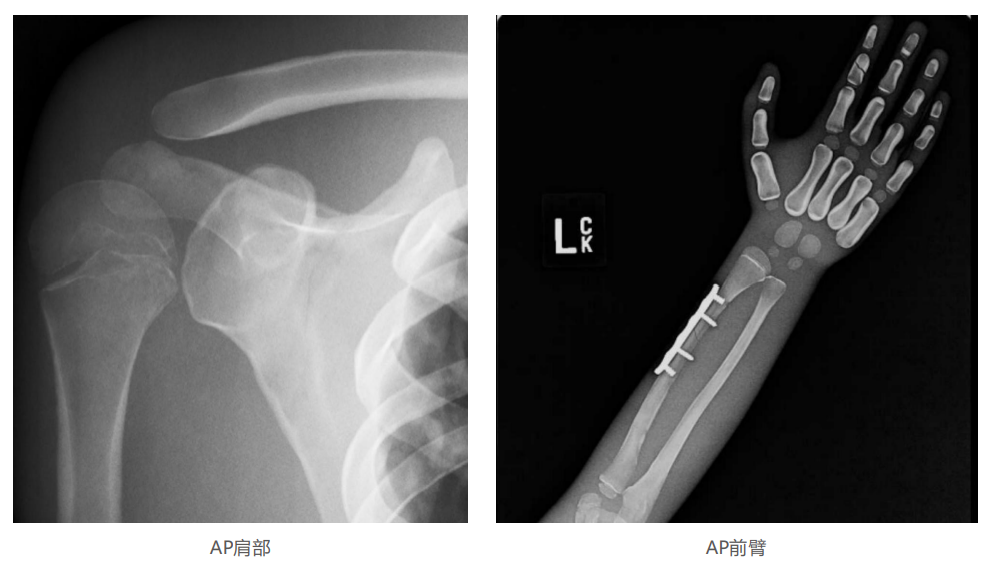

模體的大小和結構都代表了人體模體,使其便攜和易于定位。包括頭、胳膊和腿在內的整個身體。該系列包括六個部分的模體可單獨或作為一個完整的集合。

右肢有伸直或彎曲兩種配置。左臂和左腿可選伴有或不伴有內嵌骨折。

骨折版本包含最常見的人體骨折類型 ,包括脛骨扣帶骨折和腓骨普通骨折;

第一跖骨骨折;橈骨切開復位骨折 ,第二中間趾骨常見骨折。組件由適當的聚氨酯和環氧材料制成,模擬人體組織的X射線衰減特性,用于診斷和治療能量范圍(50 keV - 25 MeV) 。 材料經久耐用 ,耐沖擊,適合連續搬運。透明的軟組織有助于解剖標志的視覺指示。

? 左附件五種最常見的骨折;